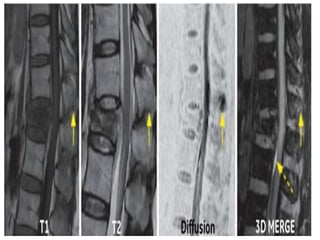

ESPONDILODISCITE